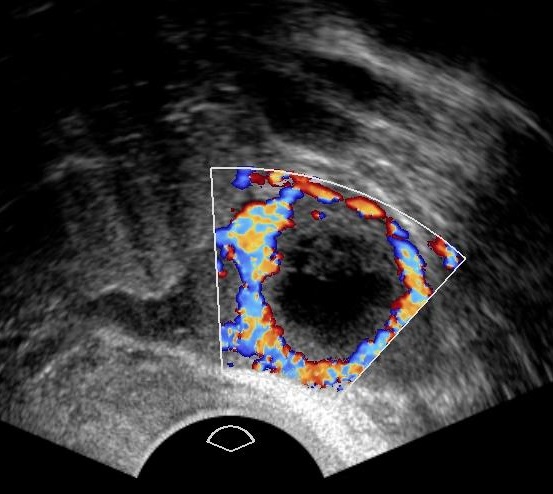

Color doppler signals may help in the diagnosis of the tubal ectopic pregnancy as they are clearly separated from ovarian tissue (Alkatout, I et al., 2013).

Keep in mind that both the corpus luteum cyst and the tubal ectopic may have similar appearance and both demonstrate ring-like color flow patterns (Fukami, T et al., 2006).

Color doppler of the same ectopic.

Color doppler of a corpus luteum graviditatis.